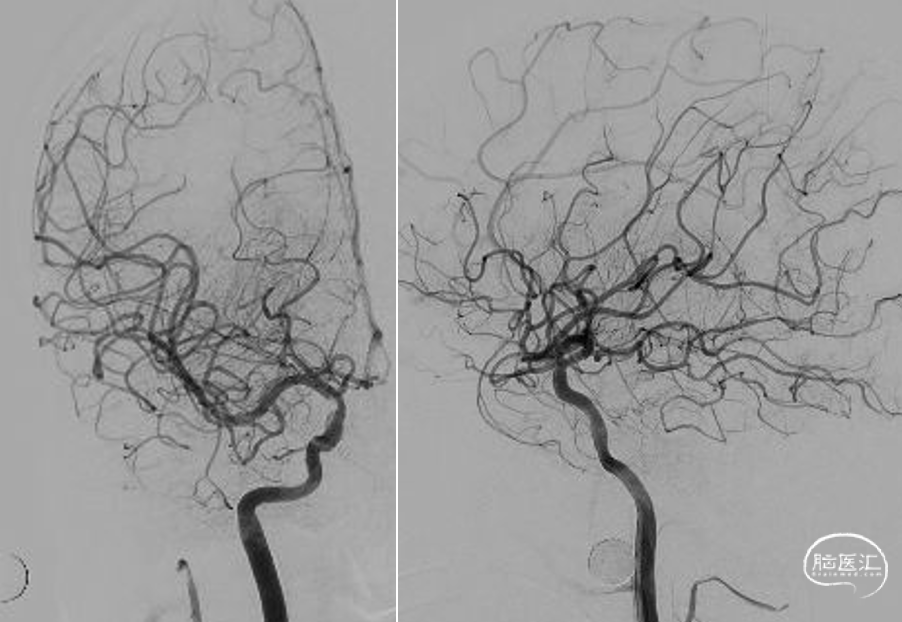

工作角度造影示:支架完全打开,贴壁良好。

术后正侧位及工作角度造影:支架贴壁良好,血流通畅。

术后查体:神志清,精神可,双眼左侧偏盲,无凝视,左侧上肢肌力2级,下肢肌力3级。血红蛋白90g/L。阴道少量出血。NIHSS评分:7分(视野:2分,肢体:5分)。

出院前复查头CT:

出院前查体:神志清,精神可,双眼左侧偏盲,无凝视,左侧上肢肌力3+级,下肢肌力4_级。无阴道出血。NIHSS评分:4分(视野:2分,肢体:2分)。